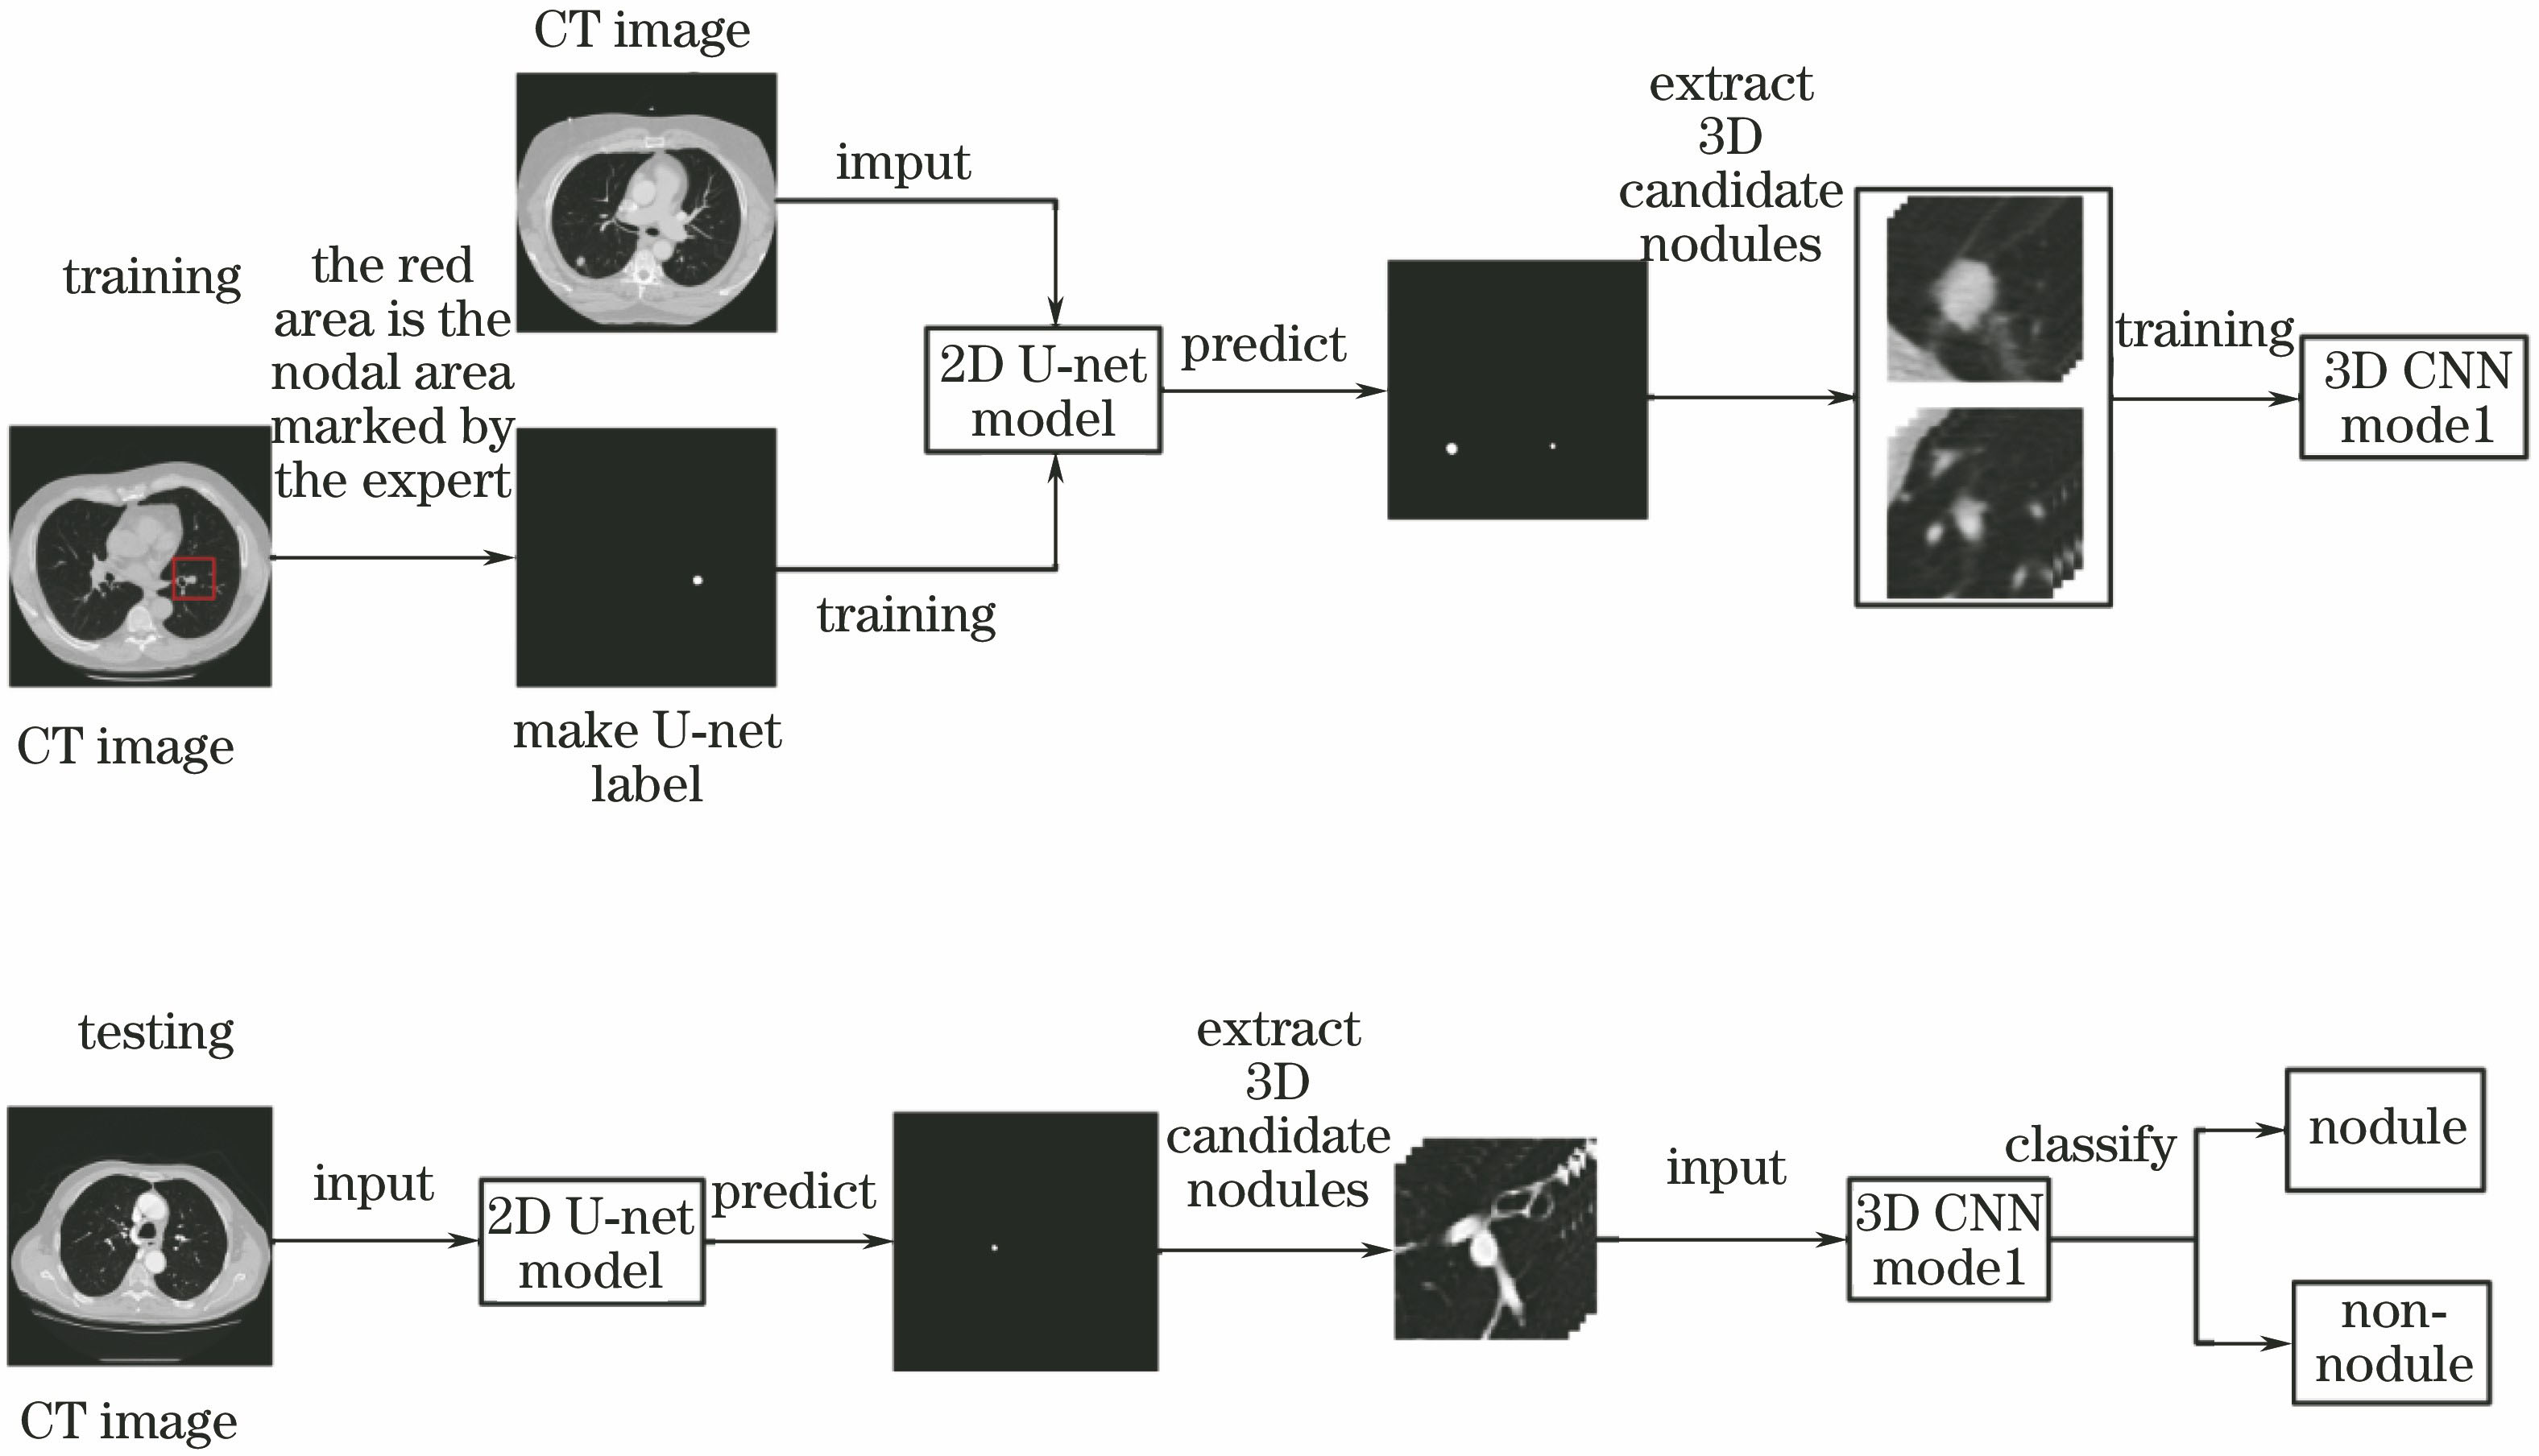

二维和三维卷积神经网络相结合的CT图像肺结节检测方法  下载: 2881次

Detection of Pulmonary Nodules CT Images Combined with Two-Dimensional and Three-Dimensional Convolution Neural Networks

苗光, 李朝锋. 二维和三维卷积神经网络相结合的CT图像肺结节检测方法[J]. 激光与光电子学进展, 2018, 55(5): 051006. Guang Miao, Chaofeng Li. Detection of Pulmonary Nodules CT Images Combined with Two-Dimensional and Three-Dimensional Convolution Neural Networks[J]. Laser & Optoelectronics Progress, 2018, 55(5): 051006.